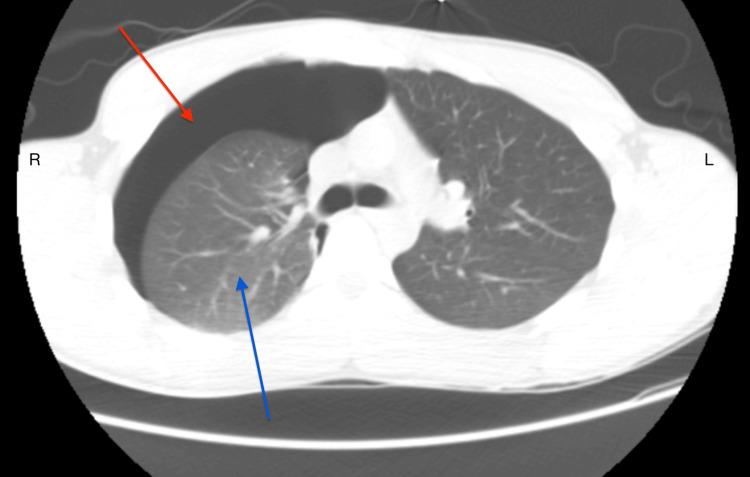

The use of cannabis for therapeutic and recreational purposes has been on the rise in recent years. This has increased the prevalence of cannabis use disorder across various demographic subgroups. A recent medical literature review describes a few cases demonstrating the association of spontaneous pneumothorax and bullous lung disease in cannabis users without concomitant tobacco use. We herein present a case report of a young male with chronic cannabis use who presented with right-sided spontaneous pneumothorax and bilateral apical blebs.

近年来,大麻用于治疗和娱乐目的的情况呈上升趋势。这导致大麻使用障碍在不同人口亚组中的患病率有所增加。最近一篇医学文献综述描述了一些案例,这些案例表明在不伴有烟草使用的大麻使用者中,存在自发性气胸与肺大疱疾病的关联。我们在此报告一例长期使用大麻的年轻男性病例,该患者出现右侧自发性气胸和双侧肺尖部肺大疱。